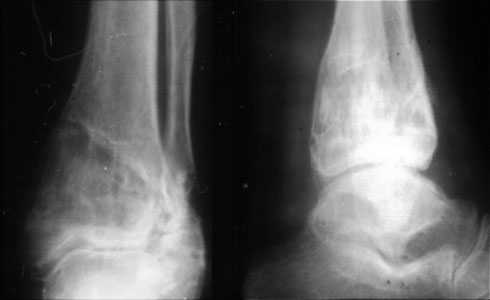

Без сомнения поддерживаю А Семенистого.Необходимо выполнить остеотомию большеберцовой кости низкую, поэтому помимо синтеза нар.лодыжки пластиной 1/3 трубки я бы запланировал синтез большеберцовой кости клевером LCP.Результат будет лучше.В аппарате потеряете оставшийся объём движений.С уважением

Уважаемый Александр то что вы показали это интересно, но это два разных случая. В ваших снимках большая деформация, которая требует выращивания массивного регенерата, поэтому здесь согласен лучше аппарат, а представленном случае дефект будет небольшой поэтому накостный синтез решит все проблемы за 2 недели без ключей 8*10 в течении 3-5 месяцев.Зачем себе создавать головную боль.